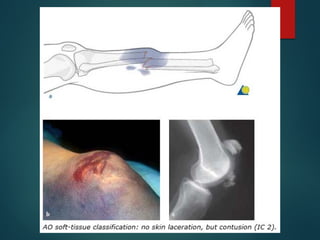

Closed skin lesions (IC)

IC 2 No skin laceration, but contusion

Closed skin lesions(IC) IC 1 No skin lesion IC 2 No skin laceration, but contusion IC 3 Circumscribed degloving IC 4 Extensive, closed degloving IC5 Necrosis from contusion